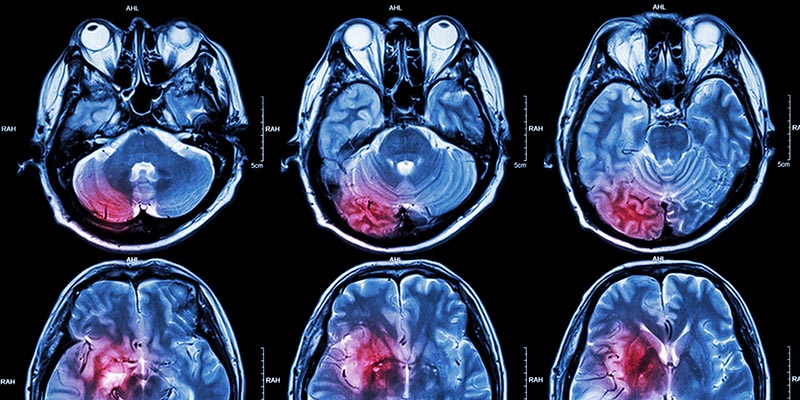

• Extensive capabilities of the latest neuroradiology imaging technologies for precise diagnoses

• Holy Cross Hospital in Silver Spring offers state-of-the-art neuroimaging techniques to diagnose stroke, tumors, and other disorders.